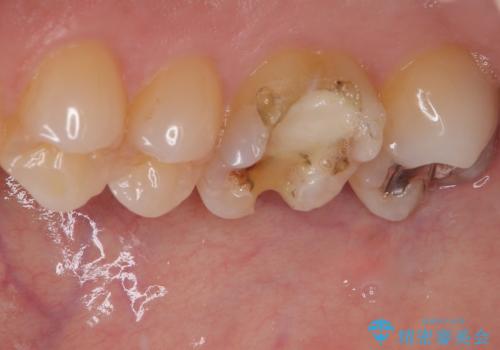

- 以前他院で治療した銀歯が外れてしまったとのことで来院された患者様です。

精査の結果、歯の神経は問題ないですが、欠損している範囲が大きいため部分的な詰め物では脱離や破折のリスクが高いため、オールセラミッククラウンによる補綴治療を行っていくこととしました。